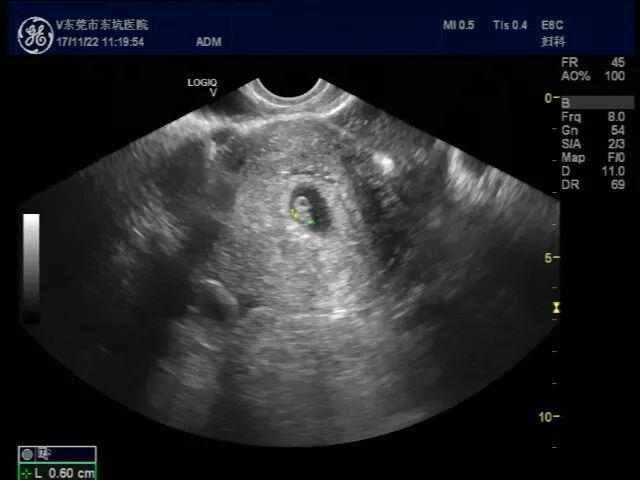

经过周主任的检查以及我院B超的详细排查,发现张小姐不仅是宫内怀孕了,宫外居然也怀孕了,周萍主任也表示在大医院从医这么多年,自然怀孕下,宫内外同时怀孕非常罕见,同时,还出现了宫外孕引起的腹腔内大出血。

宫内怀孕B超图           宫外怀孕B超